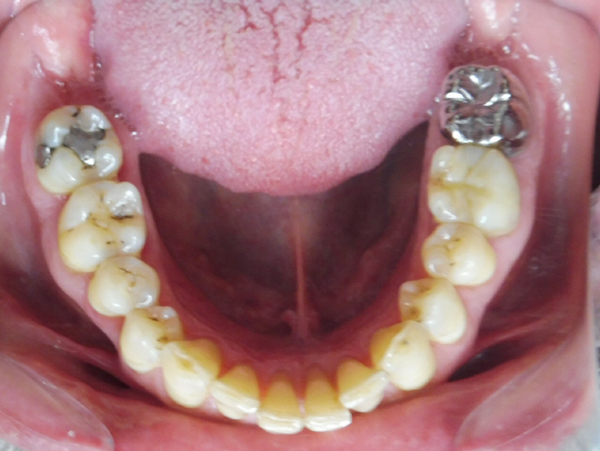

Arcade mandibulaire avant traitement orthodontique, séquelles de maladie parodontale

Après traitement orthodontique et réalisation d’une attelle fibrée (courtoisie Dr Patrick Fournier)